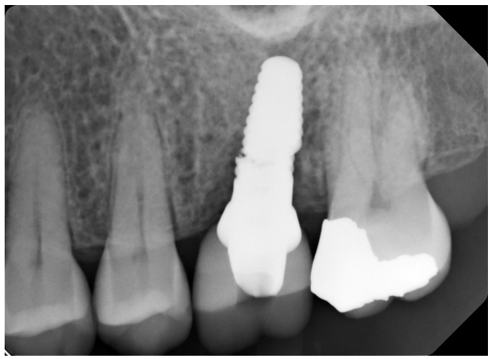

Patient presents for an emergency dental visit four months after the implant supported, cement retained crown was delivered for site #14. The patient’s CC is that she feels that her implant is loose, but she does not have any pain or bleeding. Patient reports that a few weeks ago she heard a crunch while eating a breakfast sandwich but there was no apparent mobility or pain at that time. Intraoral evaluation reveals mobility of the implant crown. Periapical radiograph confirms a catastrophic implant fracture (Fig 6).

Figure 6: Abrupt fracture of zirconia implant.